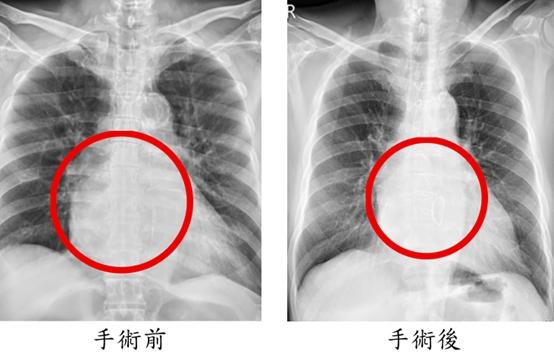

手術歷時8小時,依序完成冠狀動脈繞道手術、僧帽瓣修補、心室重建與冷凍去顫治療。術後隔天即順利移除呼吸器,再一天轉出加護病房,接受心臟復健後平安出院。術後一個月追蹤顯示,心臟收縮功能由原本32%提升至53%,瓣膜逆流消失,24小時心電圖亦未再出現心室性心律不整。陳先生恢復日常生活,並表示身體狀況比手術前更好;陳太太回憶從機上驚魂到返台治療的過程,對醫療團隊的專業與細心深表感謝與安心。